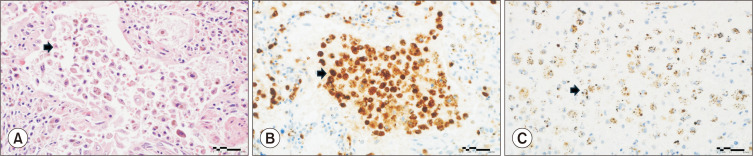

赫尔曼斯基-普德拉克综合征(HPS)是一种罕见的遗传异质性常染色体隐性遗传疾病,可影响包括肺部在内的多个器官。在 HPS-PF 病例中,肺纤维化之前会出现局部炎症。我们介绍了一例 HPS-PF 病例,该病例的组织学证据显示,细胞外陷阱(ETs)缠绕巨噬细胞,导致细胞死亡,这一过程被称为 ETosis。据我们所知,ETosis 以前从未在 HPS-PF 患者中报道过,它可能是这些患者肺纤维化的一种发展机制。我们需要进一步研究探讨 ETosis 与 HPS-PF 之间的潜在联系,因为这种认识可能有助于深入了解疾病机制,并为开发新型治疗方法铺平道路。

Hermansky-Pudlak syndrome (HPS), both alone and in conjunction with pulmonary fibrosis (HPS-PF), is a rare, genetically heterogeneous, autosomal recessive disorder that affects multiple organs, including the lungs. In cases of HPS-PF, pulmonary fibrosis is preceded by local inflammation. We present a case of HPS-PF that exhibited histological evidence of extracellular traps (ETs) ensnaring macrophages, leading to cell death in a process known as ETosis. To our knowledge, ETosis has not been previously reported in the HPS-PF population and may represent a mechanism by which pulmonary fibrosis develops in these patients. Further research is needed to explore the potential connection between ETosis and HPS-PF, as this understanding could offer insights into the disease mechanism and pave the way for the development of novel treatment modalities.